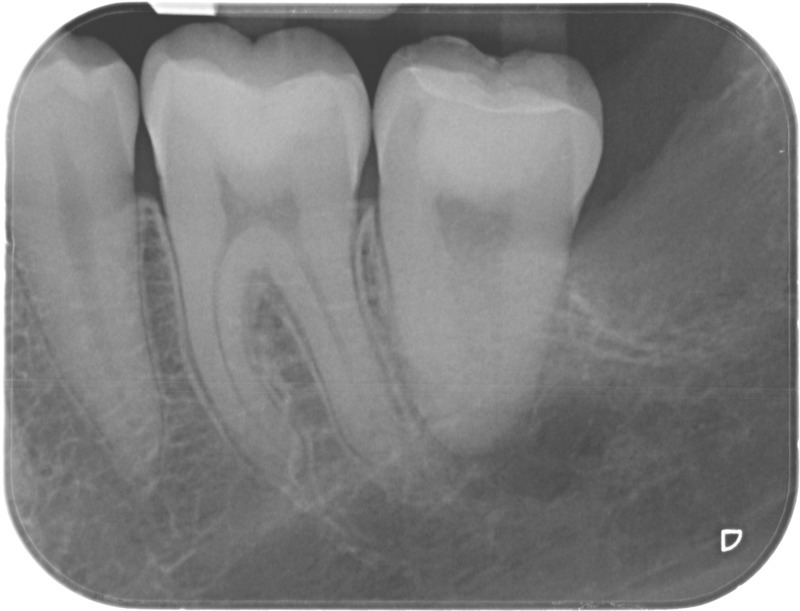

• Reprise de traitement endodontique : La manœuvre consiste à retourner à l’intérieur des racines d’une dent déjà traitée. Il arrive occasionnellement qu’une nouvelle inflammation se déclare suite à une reprise de carie ou une fracture de la dent, ou si le premier traitement endodontique est incomplet. Après s’être assuré que la dent lésée était conservable, il convient de désinfecter de nouveau le réseau canalaire parfois très complexe. La nouvelle obturation des canaux devra être protégée aussi rapidement que possible pour éviter une éventuelle contamination bactérienne.

Avant